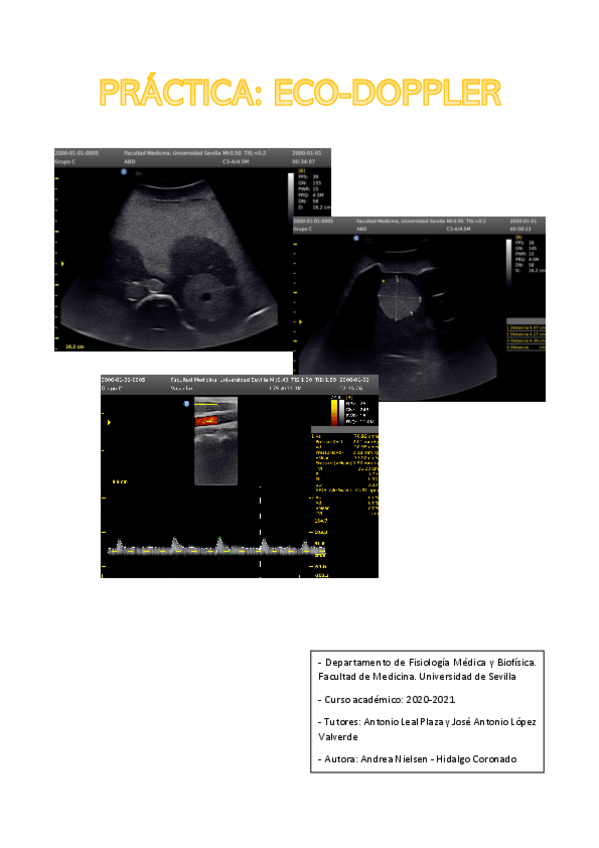

Practica-Ecografia-Doppler.pdf